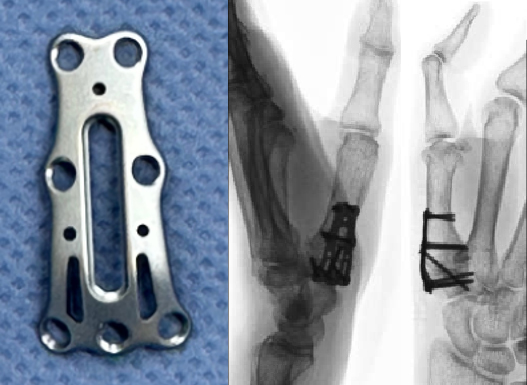

院長は日本で最初の母指CM関節固定術専用のプレートシステム (CMFiX)を2022年に開発しました。

このプレートシステムは現在、全国の大学病院や基幹病院で数多く使用されるようになっており良好な治療成績が報告されています。

母指CM関節固定術は、軟骨が摩耗して痛みや変形が強い関節をプレートやスクリューで固定する手術です。